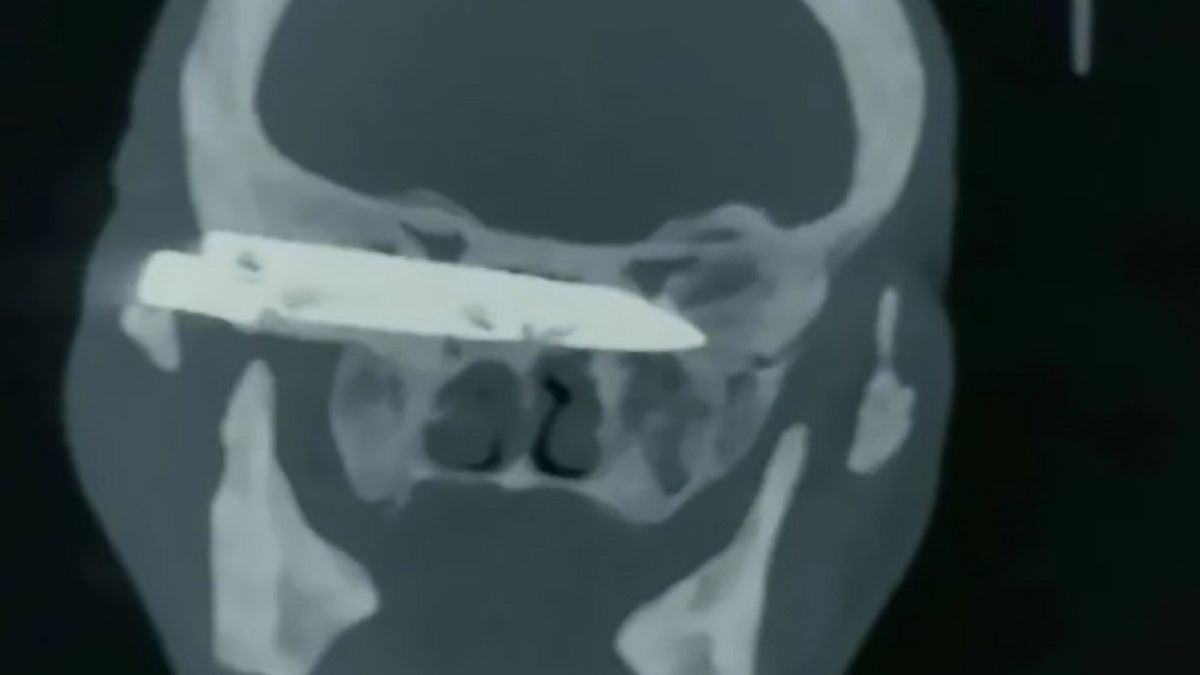

W połowie lat 90. pan Duorijie został napadnięty - napastnik wbił mu nóż w głowę o długości czterech cali (ok. 10 centymetrów). Lekarze nie mogli usunąć ostrza zaraz po incydencie więc mężczyzna żył z nim przez 26 lat.

Lekarze zainteresowali się tym przypadkiem w marcu tego roku, kiedy zwiedzali jedną ze wsi, na których mieszkał mężczyzna z nożem w głowie. Uznali, że są w stanie pomóc mężczyźnie. Wkrótce ten przyjechał do Jinan i został poddany zabiegowi. Operacja została przeprowadzona pro bono. Skany zrobione tomografem komputerowym wykazały, że ostrze zostało wbite w podstawę czaszki pacjenta, przylegało do oczodołu i naciskało na nerw wzrokowy.